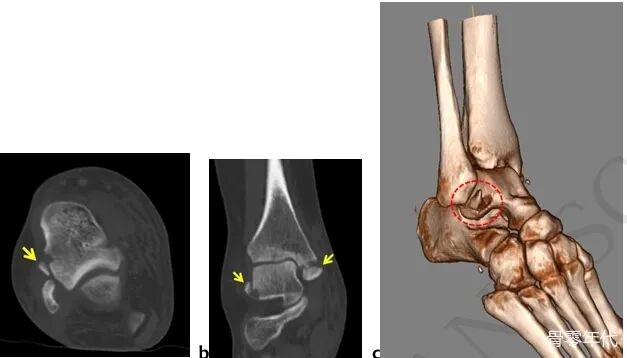

一名34岁的女性在踝关节内翻扭伤后立即入住我们的急诊科。就诊时,她无法负重,脚踝严重肿胀。主动和被动踝关节运动疼痛且受限。内踝和外踝均有压痛。神经血管检查结果正常。踝关节的直接放射学检查显示移位的内踝骨折和腓骨尖端的骨碎片(图1a,1b)。此外,斜X光片更清楚地描绘了碎片。为了了解损伤模式,进行了进一步的计算机断层扫描(CT)检查。CT显示该片段在 ATFL附着时从距骨撕脱(图 2a、2b、2c)。由于患者有移位的内踝骨折和踝关节不稳定,因此计划手术固定骨折。

踝关节扭伤的常规管理最初从休息、冰敷、抬高和压迫开始,然后是早期功能康复和支具。尽管大多数患者通过保守治疗可以完全康复,但尽管接受了初步的适当治疗,但仍有约1/3的患者继续抱怨。这些主诉通常归因于初始损伤期间发生的残余不稳定和未愈合的软骨损伤。残余的不稳定性可能是由于受伤的踝关节韧带在适当的强度和张力下未愈合,或由于撕脱骨折的不愈合而形成的。ATFL距骨撕脱骨折在目前的文献中很少报道,不幸的是,这些骨折的处理尚不清楚。由于它们相当于完全韧带断裂,因此应谨慎处理这些损伤。除了更常见的损伤模式(例ATFL破裂和ATFL 腓骨撕脱骨折)外,对于表现为踝关节外侧扭伤的患者,还应牢记距骨撕脱骨折模式。当在腓骨尖端的踝关节X光片上看到碎片时,应进行先前描述的特殊斜视图,以揭示碎片的正确来源。如果碎片足够大以进行螺钉固定,则固定这些骨折可以防止残余的不稳定性。